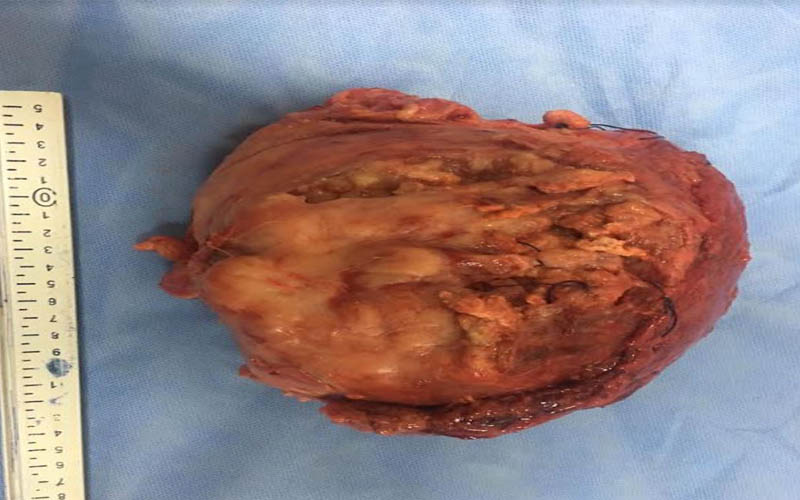

أعلن الدكتور هشام مختار حمودة رئيس قسم جراحة المسالك البولية والكلى بجامعة أسيوط ومدير مستشفى المسالك البولية والكلى الجامعي بأسيوط عن نجاح فريق طبي بالقسم في استئصال ورم سرطاني بالمثانة البولية والذي بلغ حجمه 15سم ووزنه 7كجم ،وذلك بعد إجراء عملية جراحية معقدة لاستئصال الورم لمسن يبلغ من العمر 60 عاماً والتي استغرقت6ساعات متواصلة وذلك بمستشفى جراحة المسالك البولية والكلى الجامعي ، جاء ذلك تحت رعاية الدكتور طارق الجمال رئيس الجامعة ،والدكتور أحمد المنشاوي عميد كلية الطب ورئيس مجلس إدارة مستشفيات أسيوط الجامعية .

وعن تفاصيل العملية فقد أوضح الدكتور ضياء عبد الحميد الأستاذ بقسم جراحة المسالك البولية والكلى ورئيس وحدة أورام المسالك وقائد الفريق الطبي المسئول عن العملية ، أن تلك العملية تعد من أخطر عمليات استئصال أورام المثانة البولية وذلك نظراً لكبر حجم الورم واختراقه للأمعاء والأنسجة المجاورة من الشرايين والعضلات ، مما يشكل خطورة بالغة على حياه المريض والذي تم تعرضه لظروف معينة تسببت في إهماله للمرض لعدة سنوات ، مشيراً أن ذلك تم من خلال التنسيق والتعاون مع أعضاء قسم الجراحة العامة .